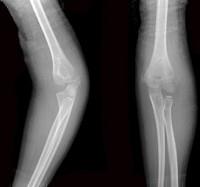

问题 6岁女性患者,因外伤后致左肘关节肿痛,活动受限,外髁局部压痛明显X线摄片如图,最合适的诊断是 ( )

选项 A、左肱骨小头骨骺Ⅳ度分离 B、左肱骨小头骨骺Ⅴ度分离 C、左肱骨小头骨骺Ⅱ度分离 D、左肱骨小头骨骺Ⅲ度分离 E、左肱骨小头骨骺Ⅰ度分离

答案 C